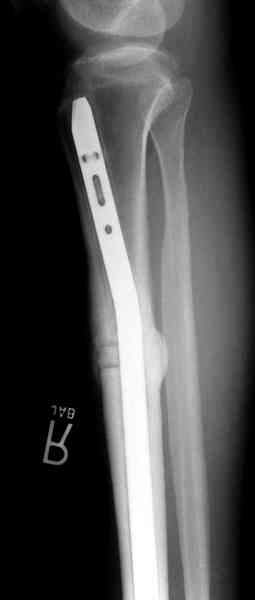

conference мы разбирали похожий случай, ложный сустав большеберцовой кости после резекции опухоли.

К нашему онкологу-ортопеду обратился больной с жалобами на боли в голени, из рассказа - год назад была сделана биопсия большеберцовой кости, но название заболевания "не запомнил”.

Оперирован в военном госпитале с заменой сегмента

аллокостью большеберцовой кости и после демобилизации явился для постоянного наблюдения по месту жительства.

В литературе "A Classic Adamantinoma Arising from

Osteofibrous Displasialike Adamantinoma in the Lower Leg: A case report and Review of the Literature похожие снимки.

Наши имели проблему со сращением, пришлось им сделать динамизацию, дополнительную аутопластику.

Снимки представлены.